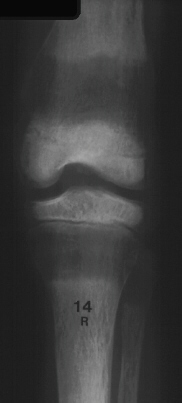

J. G. is a 14 3/12 y.o. boy who presented complaining of pain in his right leg for 9 months and contracture of the right knee which has developed over this period. There is no history of significant trauma. Born 3 weeks premature with bilateral renal hypoplasia and a seizure disorder. Three renal transplants have failed and he currently receives peritoneal dialysis four times a day. Stunted growth and developmental delays during childhood include short stature, standing at 16 months and walking at 2 years. He sustained a right tibia and fibula fracture 6 years prior to presentation after minimal trauma.

PHYSICAL EXAM: 5'4". Poor dentitia, right knee 15 degree flexion contracture, painful ROM of right hip and knee.

RADIOGRAPHIC EVALUATION: Osteopenia, subcortical resorption, lucent metaphyseal bands, widening of metaphysis and "rugger jersey spine".

RADIOGRAPHIC:

Early - Osteopenia

Thinning of cortices and trabeculae gives "ground glass" x-ray

Salt and pepper skull

Physeal thickening and fraying of metaphysis, no cupping

Late epiphyseal ossification

Epiphyseal Slips - Preschool age: Proximal and distal femoral and distal tibial

Older Children: Proximal femoral and distal forearm

Late - Secondary hyperparathyroidism

Subperiosteal cortical resorption - Distal phalanx, end of clavicle, ischium, pubis, SI joints, metaphyseal-diaphyseal junction of long bones

Lucent metaphyseal bands - Growth zone changes are the best indicator of severity of secondary hyperparathyroidism

Bowing of long bones

Rugger Jersey spine - Osteosclerosis of the end plates of the vertebral bodies

Brown Tumor (rare) - Rib or jaw

Amyloidosis - Multiple bone cysts: Metacarpals, hip, wrist, prox humerus, pubic rami and proximal tibia.